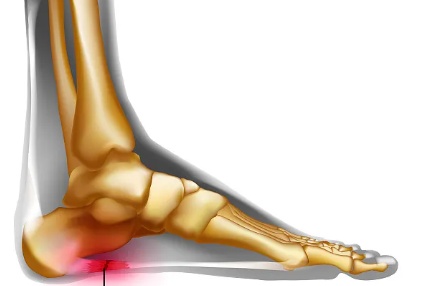

足底筋膜位于脚底,连接足跟和脚趾,平时负责支撑足弓、缓冲压力。长期受力过多、反复牵拉后,筋膜在足跟附着处就容易劳损,时间久了,就会出现疼痛。最典型的表现,就是晨起第一步痛、久坐后起身痛、走远了更痛。